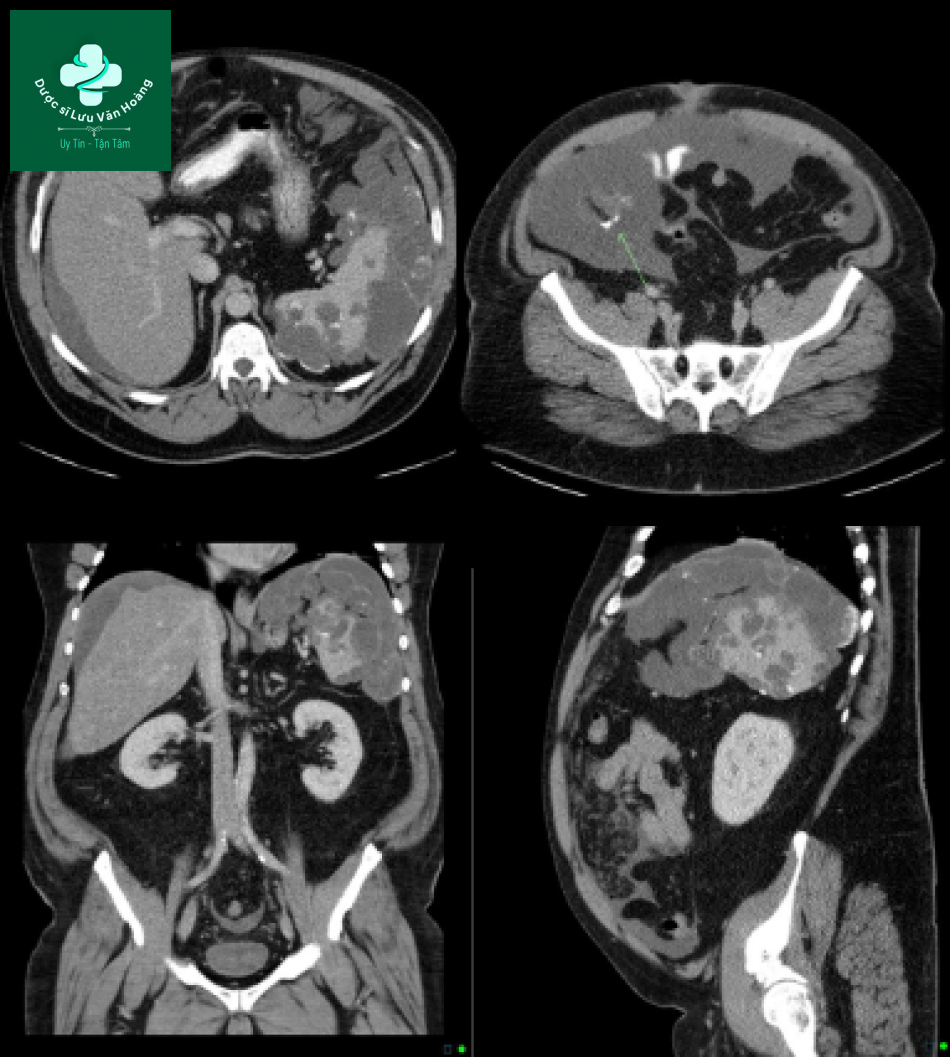

Bệnh nhân nữ, 50 tuổi. Hình ảnh CT có nhiều khối giảm tỷ trọng với dịch đóng ngăn ở phúc mạc, mạc treo, mạc nối tạo hình vỏ sò ở bề mặt các tạng, đặc biệt ở gan. Không thấy hình ảnh vôi hóa.